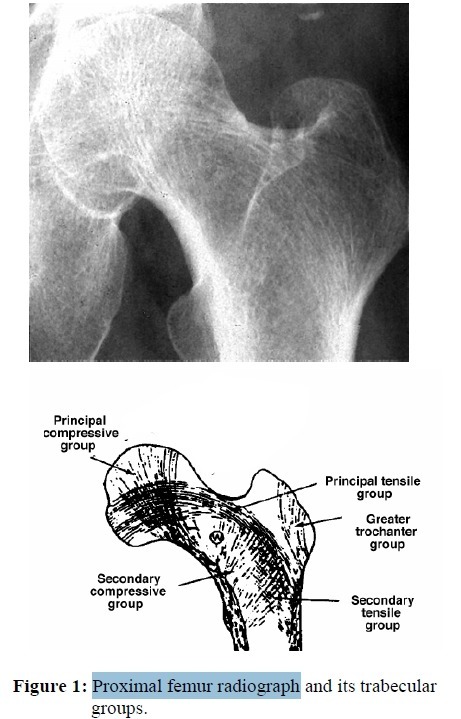

뼈에서 골소주(tension and compression trabeculae) 배열이 존재

- 뼈의 배열(tension trabeculae and compress